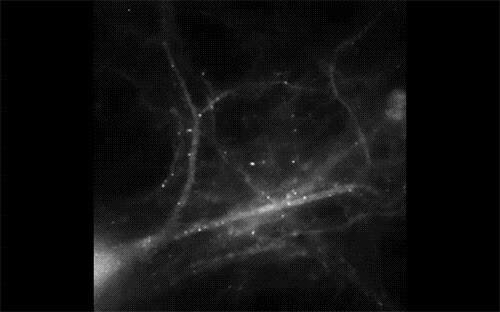

12.神经细胞与钙离子的精彩邂逅

钙离子一直都是神经细胞最重要的“信号离子”,通过显微注射技术将钙离子探针放进神经细胞中,使得探针和钙离子相互作用而产生荧光,钙信号在神经细胞中会像水波一样迅速向外扩散。